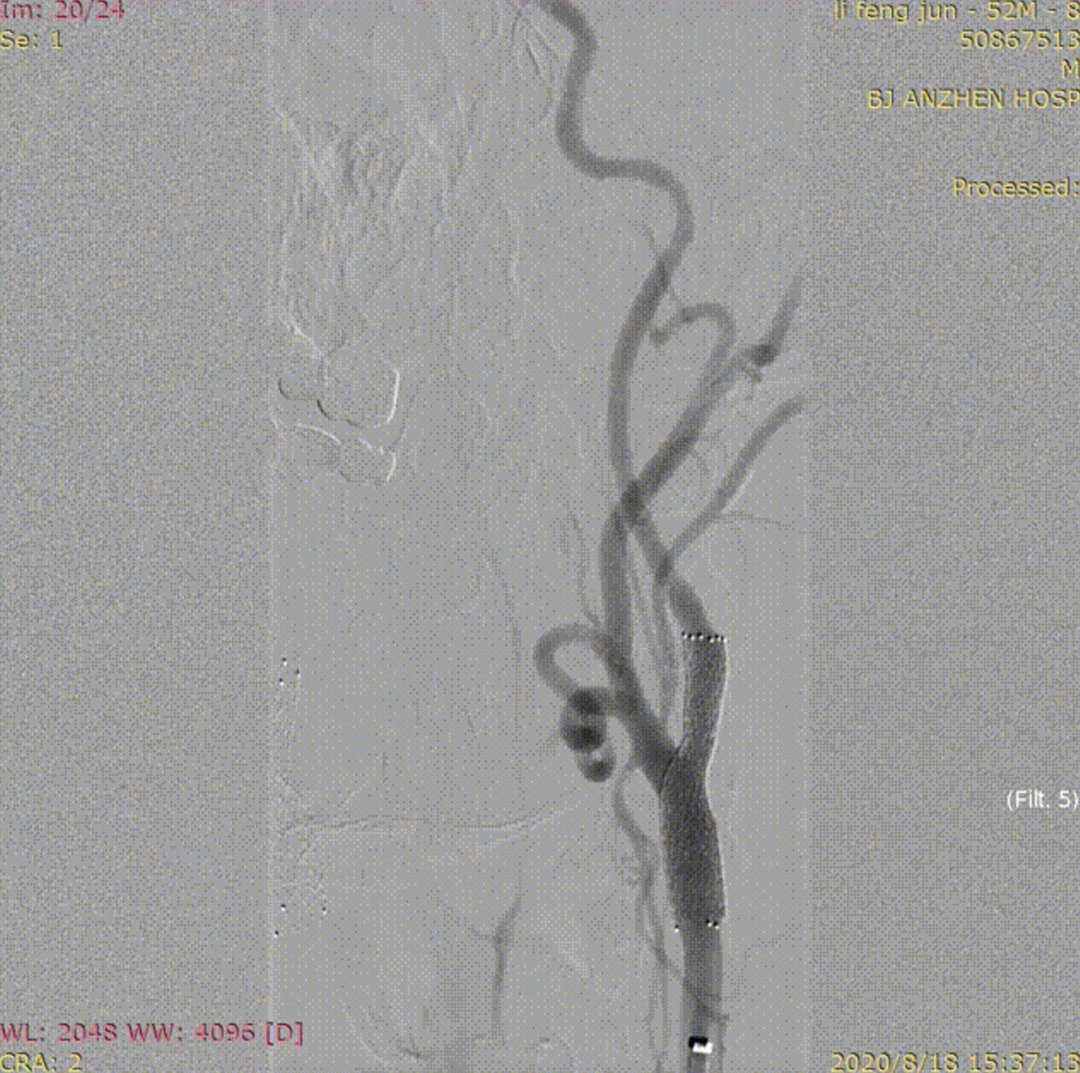

病例2:52岁男性,发作性胸痛2年,体检发现双侧颈动脉狭窄,冠脉情况严重,先行PCI,后行双侧CAS,先右后左,术后复查颈动脉支架通畅。

右侧术前

右侧术后

左侧术前

左侧术后